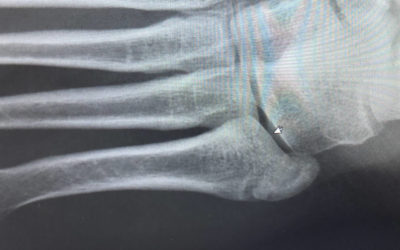

Have I Broken My Toe?

What is this picture? Below is an ultrasound of a ladies little toe. Many people think that an X-ray is needed to show a break in the bone but this isn’t the case. The picture below is proof. It shows there is a break and that it hasn’t healed. Sometimes just knowing...

Diagnosing A Stress Fracture With Ultrasound

Ultrasound has been discussed on many occasions in our previous blog posts but we haven’t gone into any detail as to the effectiveness of looking at stress fractures. Most people consider a break to be seen on an X-Ray, or...